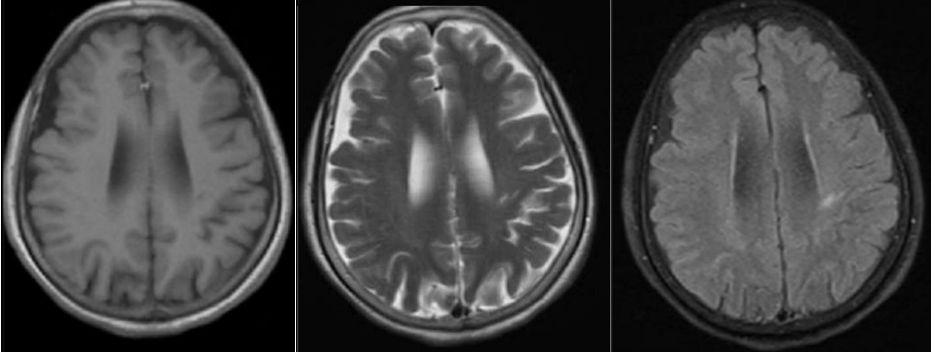

病例11

昏迷1天。

答案:脑梗死(双侧前循环闭塞)。这个病例没有提供年龄,性别等资料。影像提示皮层花边征,基底节区也受累。在第27期晨读总结过皮层花边征口诀:低糖高氨上吊死;疯牛病脑偏头疼;假酒中毒持续抽;一氧化碳来凑数;低钠渗透髓鞘脱。提醒各位老师看到类似影像不要忘记有可能是双侧前循环大血管闭塞引起。详见甲硝唑相关脑病、脑腱黄瘤病 、静脉性脑梗死丨3分钟读片·27期。